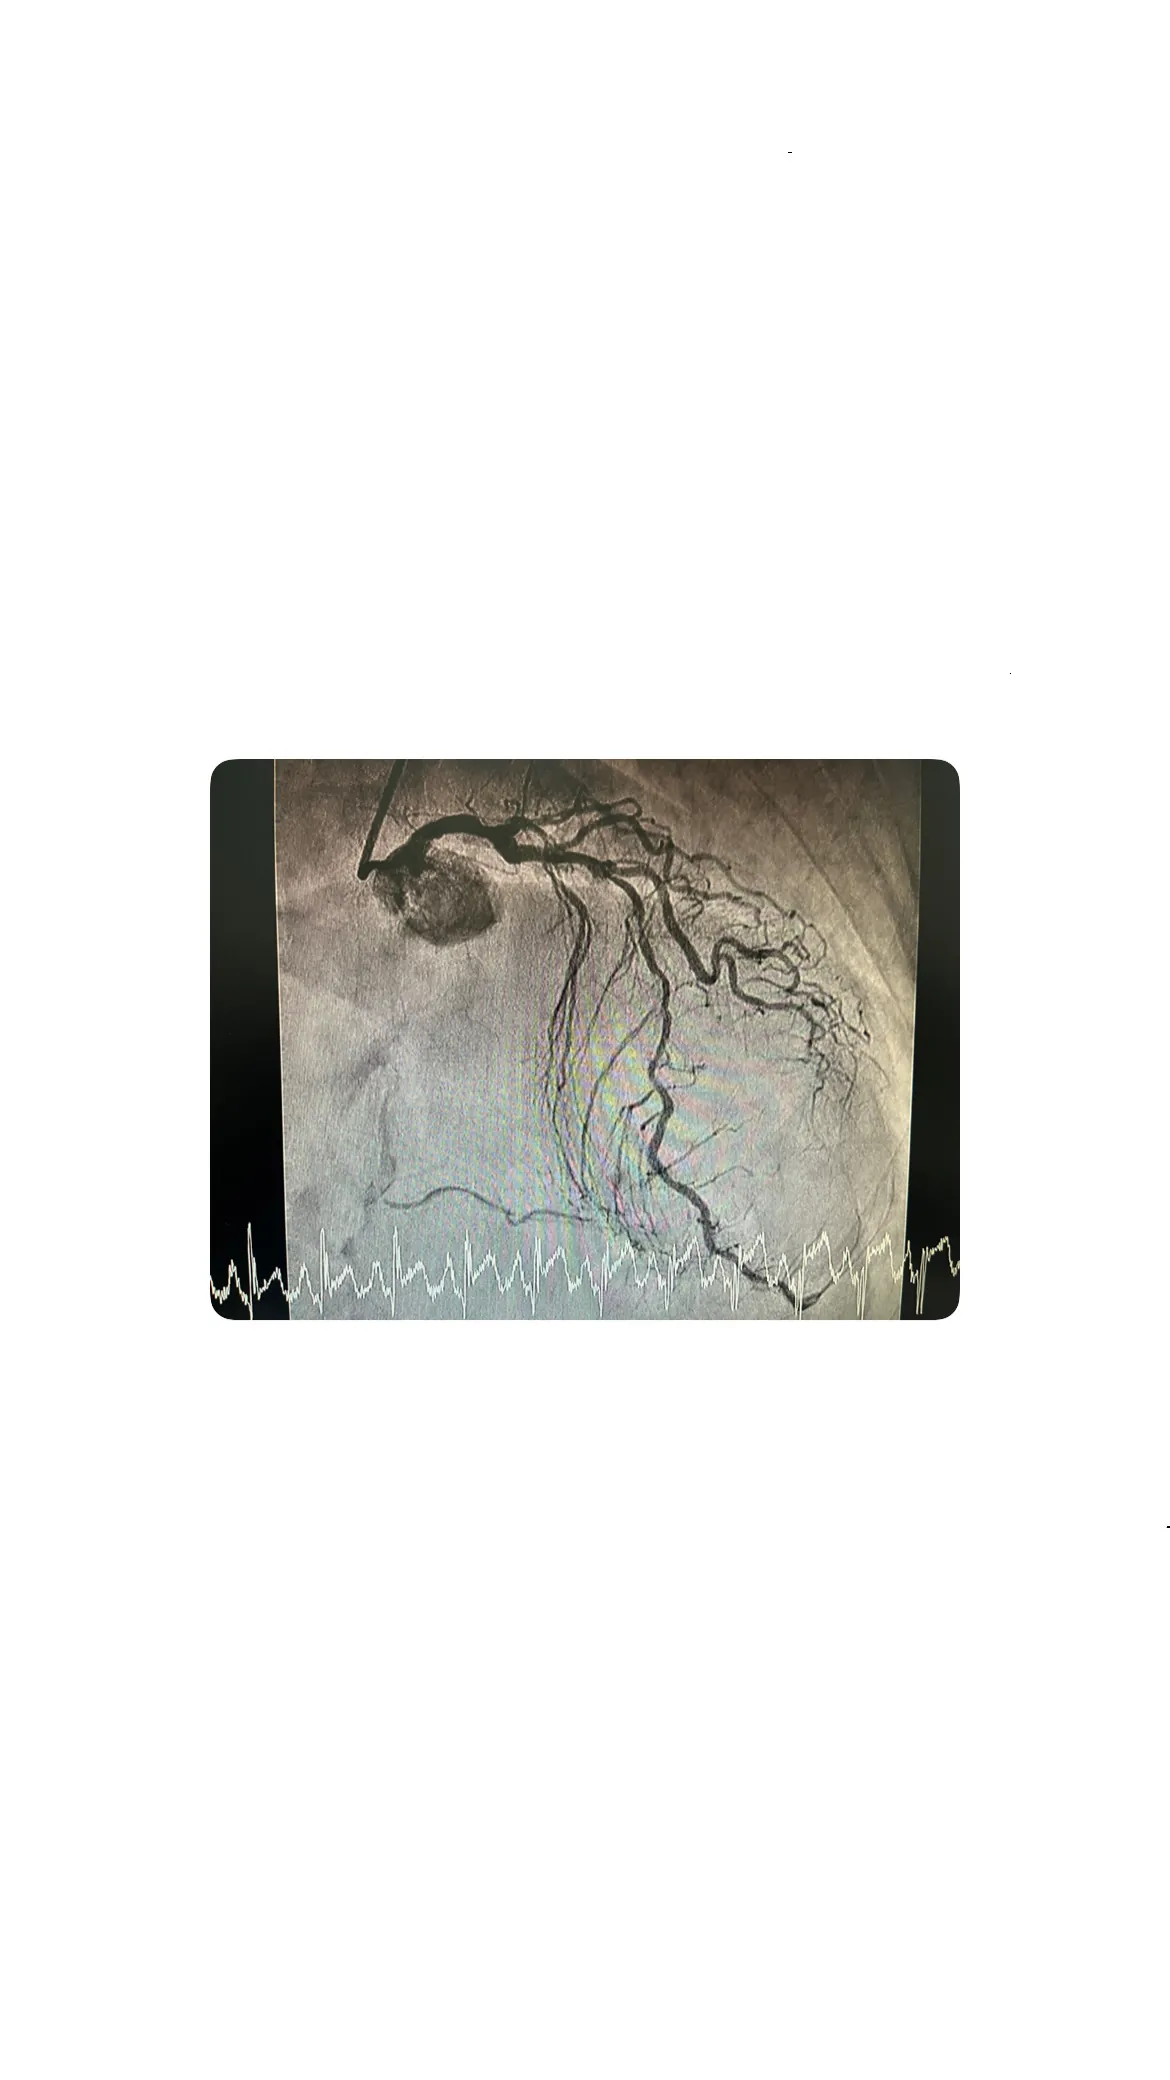

Cateterismo por radial derecha: técnica y hallazgos

El cateterismo se realizó a través de la arteria radial derecha, una técnica menos invasiva que permite una recuperación más rápida.

Enfermedad de la descendente anterior y coronaria derecha

Se identificó enfermedad en la arteria descendente anterior y una lesión a nivel medio en la coronaria derecha, junto con una oclusión crónica distal. Estos hallazgos complican la situación, requiriendo un enfoque integral para la revascularización.

Qué significa una lesión en tronco común y 3 vasos

Una lesión de tres vasos implica un riesgo elevado de complicaciones cardíacas severas. La afectación de múltiples vasos añade complejidad al tratamiento y aumenta el riesgo de eventos adversos.